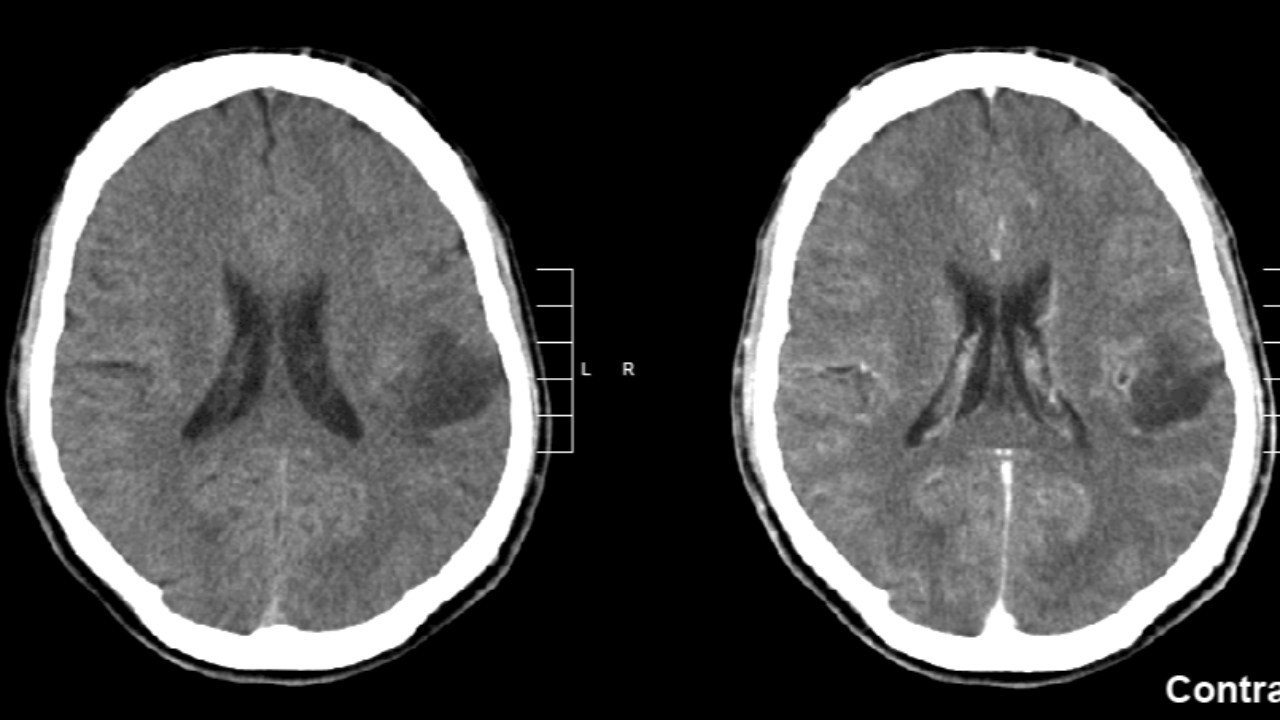

سرطان الدماغ أو الورم الدبقي النخاعي مرض قاتل ونادر لكنه قاتل بشكل مأساوي وهو واحد من أكثر أشكال السرطان المخيفة لدى الأطفال، غير أن حالة تعافي استثنائية لطفل أثارت آمالًا كبيرة في المجتمع الطبي البحثي الفرنسي.

والورم الأرومي الدبقي هو نوع من السرطان يبدأ على هيئة نمو للخلايا في الدماغ أو الحبل النخاعي، وينمو سريعًا ويمكنه غزو أنسجة الجسم السليمة وتدميرها.

يتكون الورم الأرومي الدبقي من خلايا تسمى الخلايا النجمية تدعم الخلايا العصبية.

وقد تحدث الإصابة بالورم الأرومي الدبقي في أي مرحلة عمرية. غير أنه غالبًا ما يصيب البالغين الأكبر سنًا والرجال في أكثر الحالات. تشمل أعراض الورم الأرومي الدبقي نوبات صداع مستمرة التفاقُم والغثيان والقيء وضبابية الرؤية أو ازدواجها ونوبات الصرع.